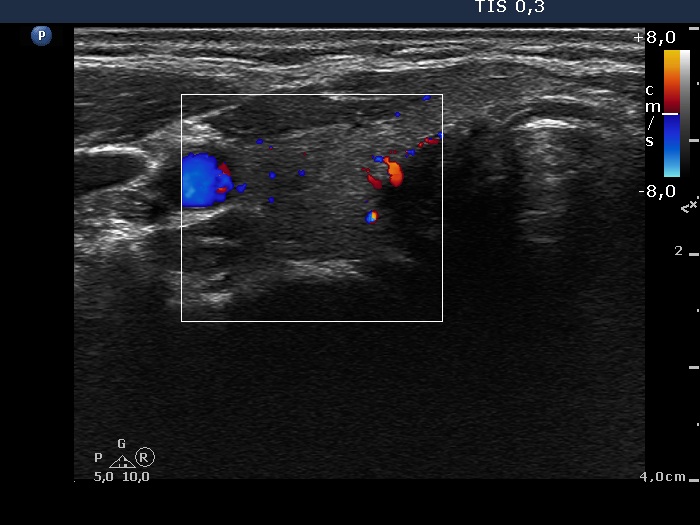

Subacute granulomatous de Quervain's thyroiditis - Case 6.

Five months after initial examination (ultrasonographic picture 4)

Right lobe, horizontal view, color Doppler mode. The vascularization is already decreased.